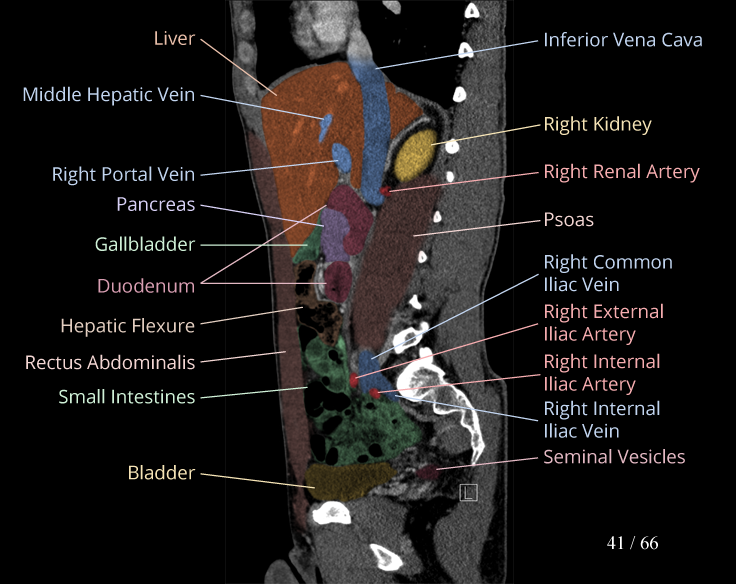

Body

Covers abdominal CT anatomy.